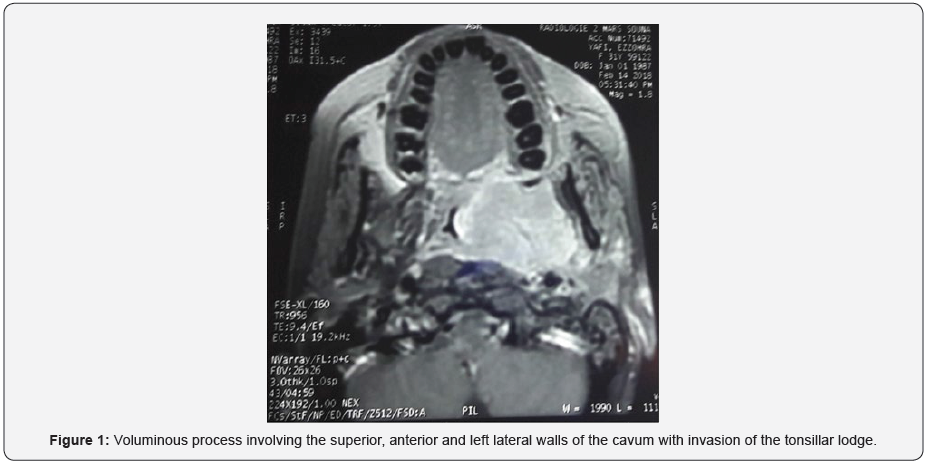

The patient has undergone a rhinocavoscopy in order to take biopsies of the lesion, for which the anatomopathological study revealed an UCNT. Then, the patient has benefited from Cervicofacial MRI to study the extension of the tumor. It has revealed voluminous process involving the superior, anterior and left lateral walls of the cavum with invasion of the tonsillar lodge and deep spaces of the face (Figures 1 & 2). The patient has received a cure of radiotherapy, and evolved well, with a rhinocavoscopy of control showing disappearance of the tumor.